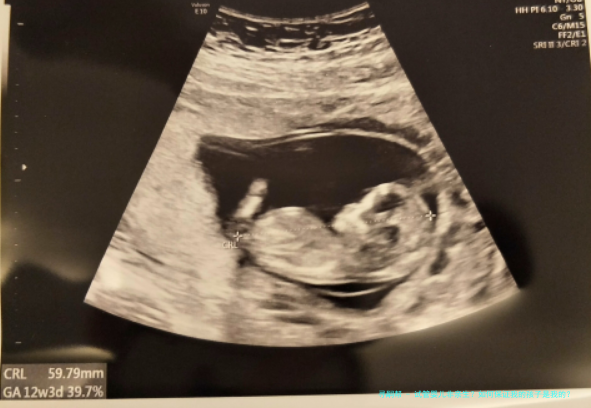

试管婴儿非亲生?如何保证我的孩子是我的?

安徽“试管婴儿出生8年后被发觉放错胚胎”事件,引发注意。试管婴儿非亲生?怎么样保证我的孩子是我的?跟着人类人类辅助生殖技术的出世,给有生育困境的患者带来希望。辅助生殖技术不只是医药学技术,更是关涉到伦理问题,该怎样保障在辅助生殖技术过程顺当进行,需要从各个环节抓起,一环紧扣一环,每一步骤都至关重要。